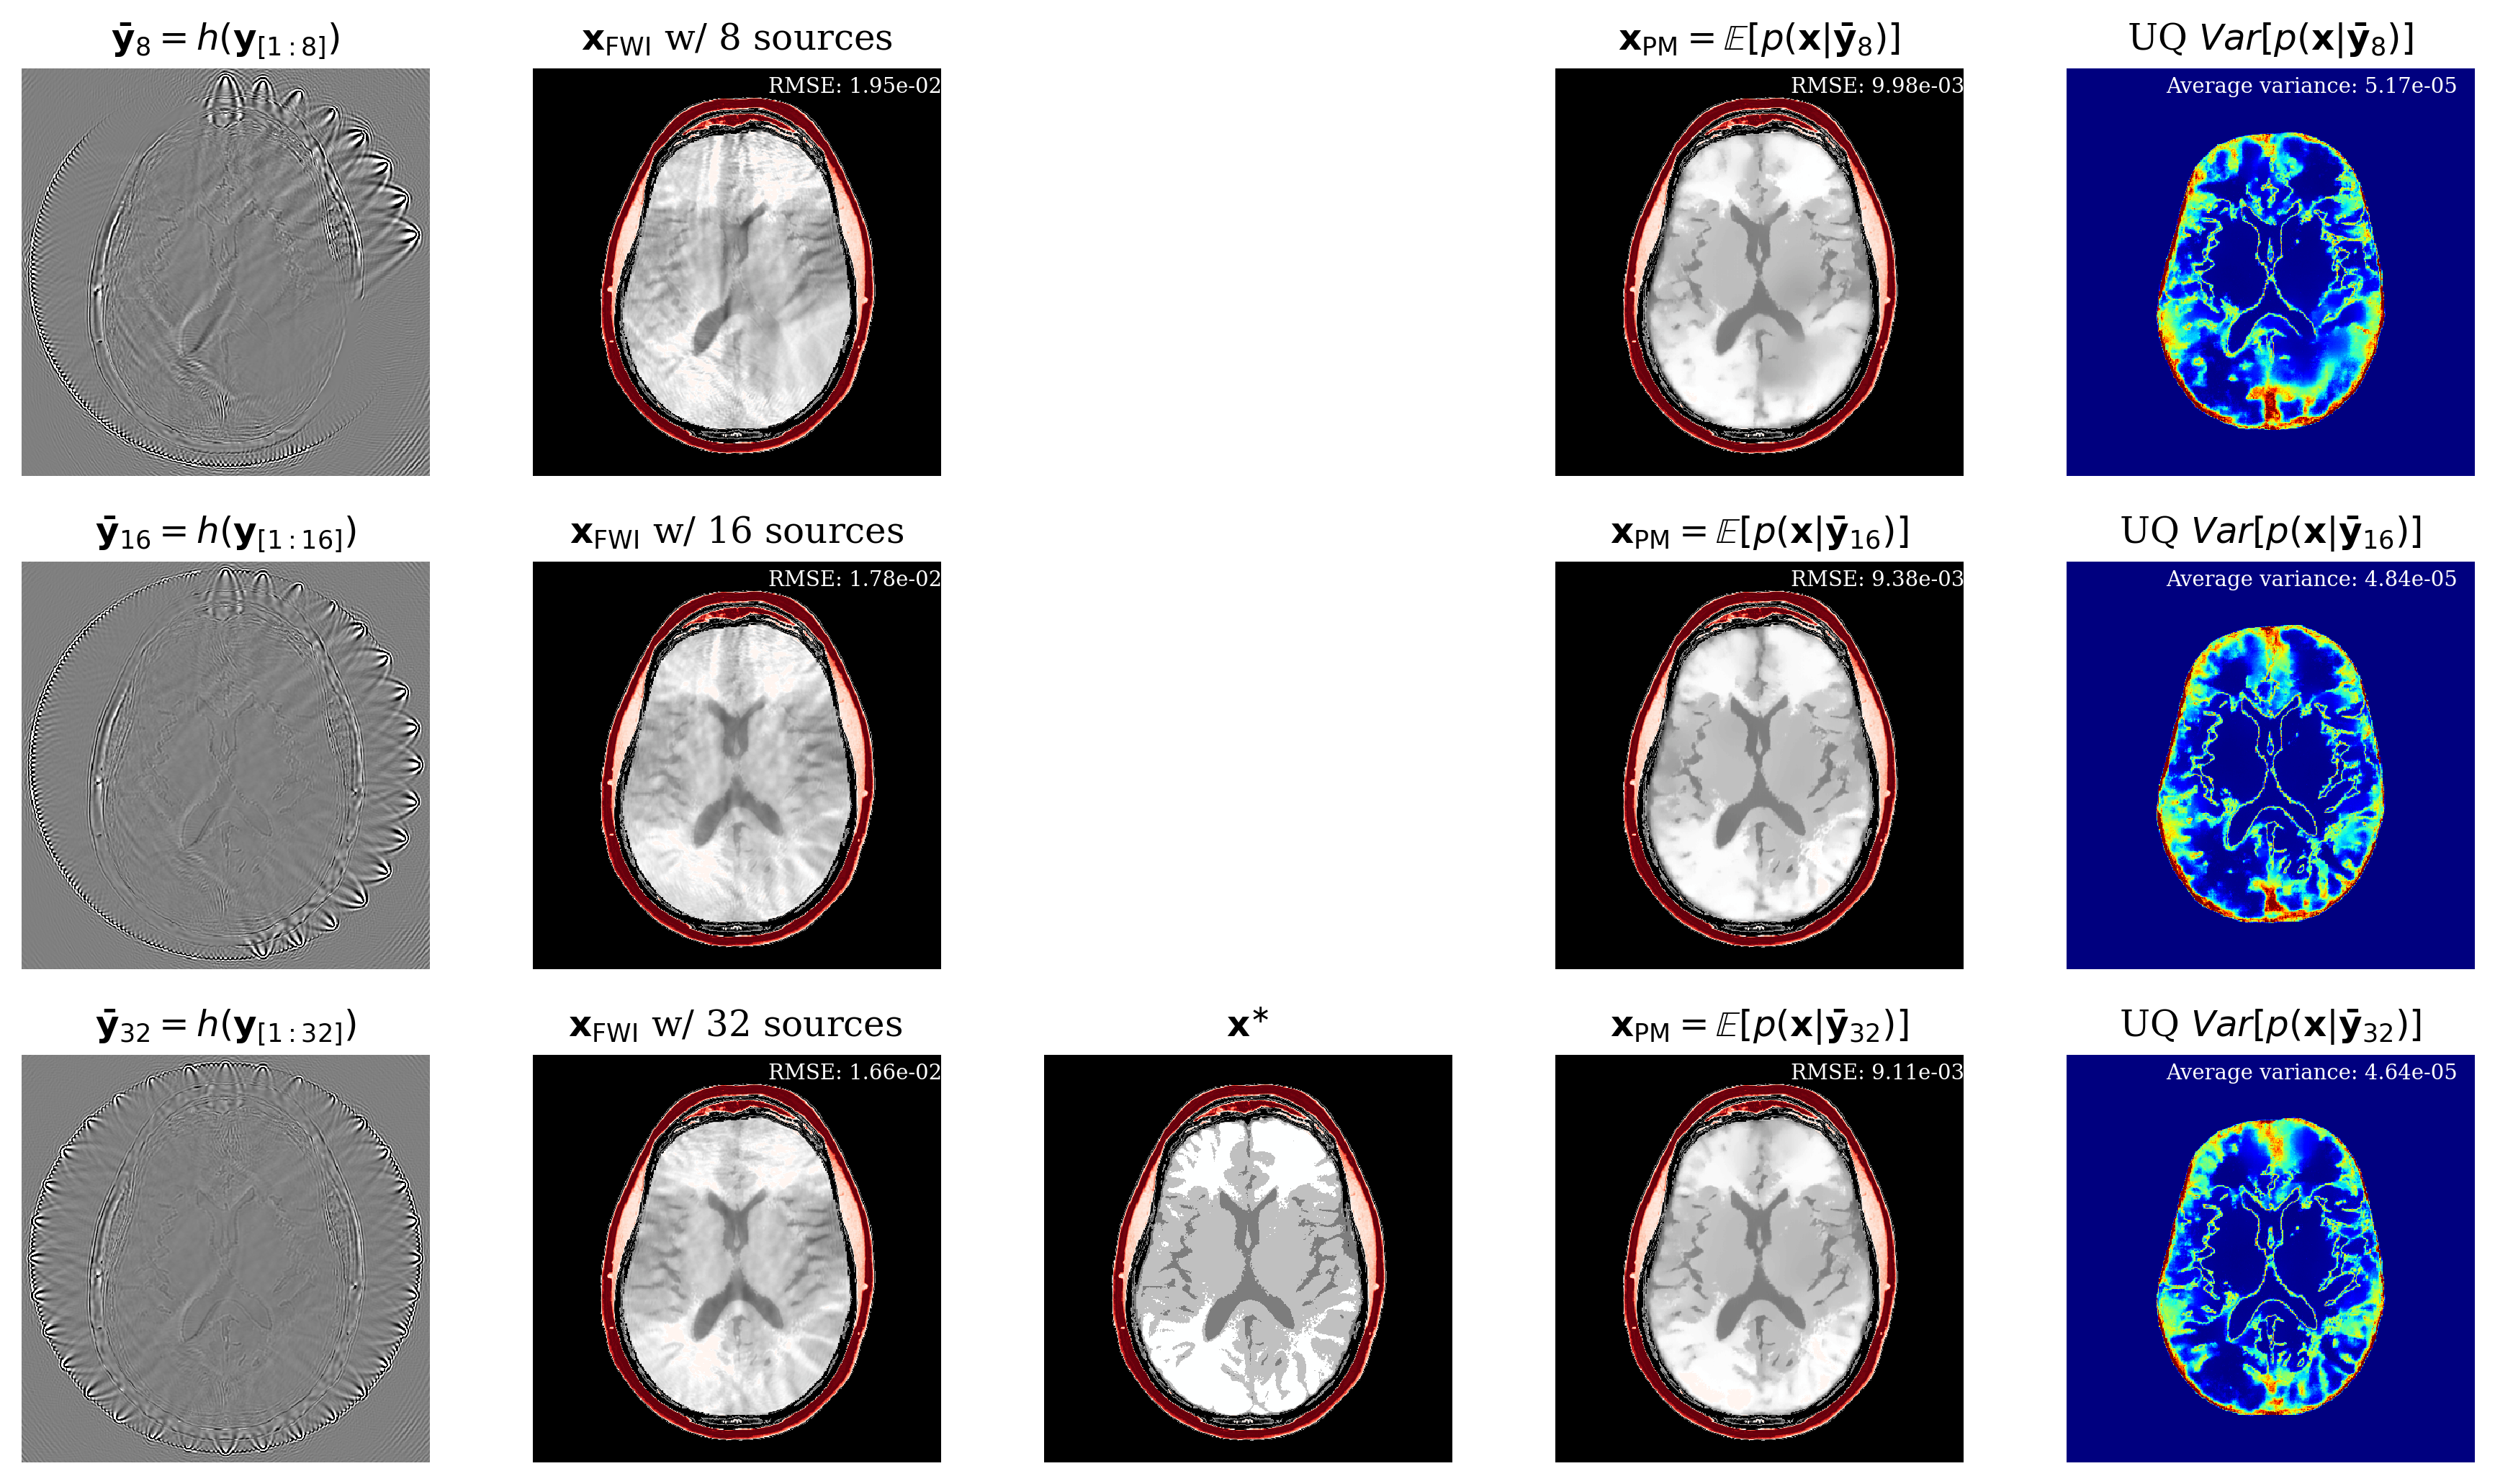

3.3 Generalization over experimental configurations

In Figure LABEL:fig:amort, we show how our method generalizes over different source configurations. Aside from handling different acquisition constraints, practitioners can also quickly prototype different configurations to decide which one meets their threshold of uncertainty.

fig:amort

(ii) Bayesian contraction: a Bayesian method needs to show contraction on the ground truth as more data is observed Ghosal and Van der Vaart (2017). Here contraction means that more data should decrease the uncertainty. Not only that, the error made should also decrease. Qualitatively we confirm this behaviour in \figurereffig:amort where increasing the number of source experiments decreases the overall uncertainty. Figures 10 and 10 show that over the test set, increasing sources shows Bayesian contraction. As a scalar measure of uncertainty, we use the sum of variance for all parameters.